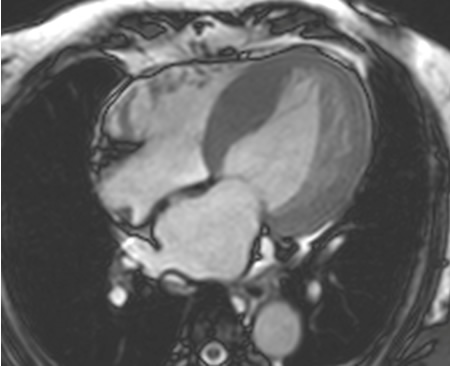

Studies have shown that CMR has a high concordance with echocardiography in measuring mitral inflow velocities and myocardial tissue velocities, in both patients and controls.[73][74][Figure caption and citation for the preceding image starts]: CMR of patient with cardiac amyloid infiltration. Following injection of gadolinium contrast, in the late phase there is sub-endocardial basal ring in the left ventricle (4-chamber view)From the collection of Dr Jessica Webb; used with permission [Citation ends].

[Figure caption and citation for the preceding image starts]: CMR of patient with cardiac amyloid infiltration. Following injection of gadolinium contrast, in the late phase there is sub-endocardial basal ring in the left ventricle (short-axis basal image)From the collection of Dr Jessica Webb; used with permission [Citation ends].